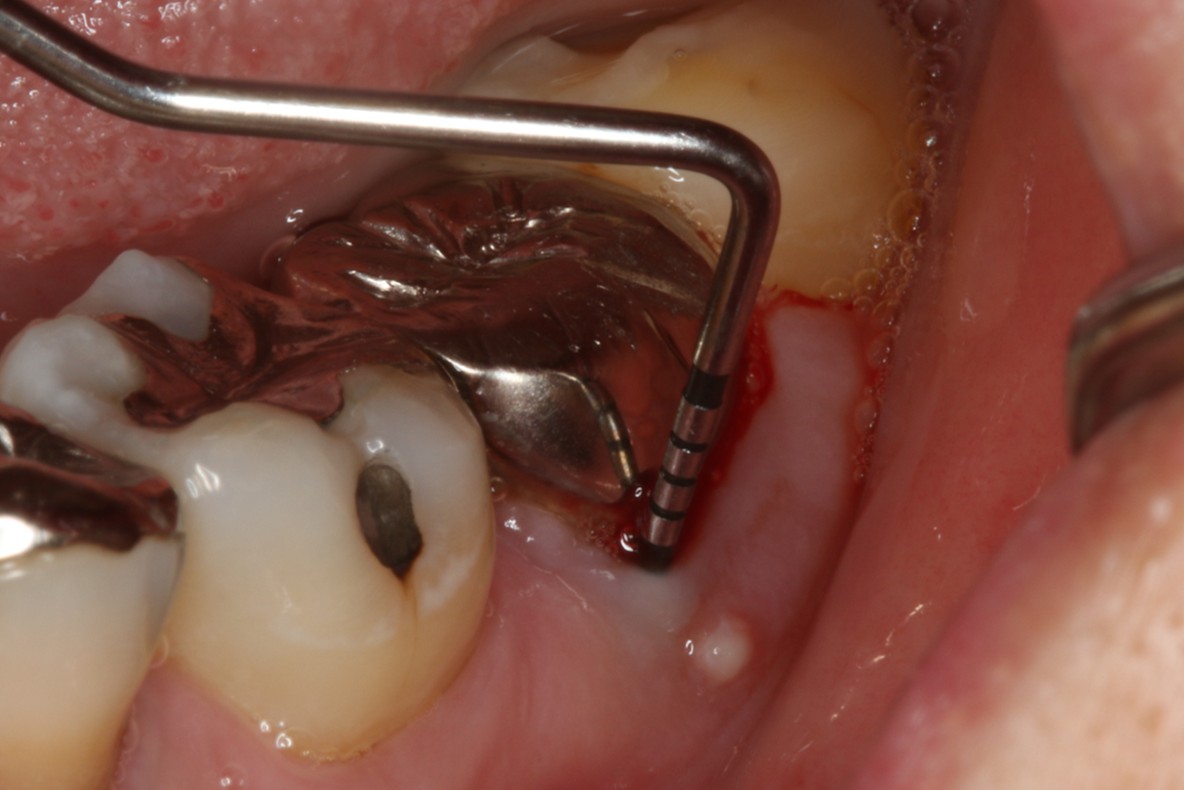

症例4

右下親知らずを右下第二大臼歯へ移植

| 患者様データ | 20代 女性 |

| 来院時の主訴 | 「右下奥歯で噛むと痛い。」 |

| 医院の診断 | 歯根破折 |

| 通院期間 | 6か月 |

| 来院回数 | 10回 |

| 治療費 | 総額:255,000円(税抜) 【内訳】 歯牙移植150,000円、ファイバーポストコア20,000円、セラミック治療85,000円 |

| リスクと副作用 | ①根管治療歯は長期的には破折するリスク ②長期的なメインテナンスが必要 ③歯根の外部吸収 |

| ここがこだわりのポイント!☝ |

抜歯が必要になった際に余っている親知らずがあれば移植歯として利用することができます。 術前に撮影したCT画像から3Dプリンターを用いて親知らずのレプリカを作製することで、親知らずが乾燥することを防ぎ、成功率が上がるよう努力しています。 |